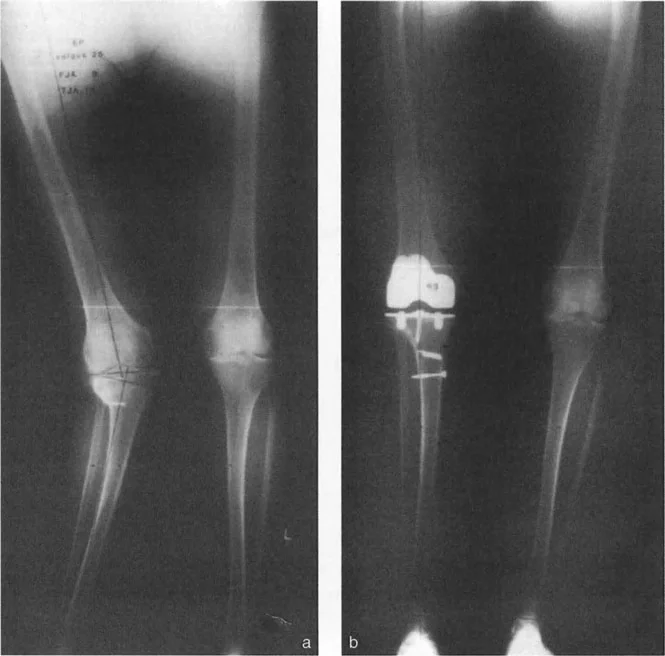

كما يتضح في الصورة الشعاعية أعلاه، فإن تحقيق طرف سفلي محاذٍ جيدًا (حيث يتم استعادة المحور الميكانيكي) في وجود تشوه في الجزء الأوسط من العظم غالبًا ما يؤدي إلى قطع داخل المفصل غير متماثلة للغاية. إذا قام الجراح ببساطة بالقطع بشكل عمودي على المحور الميكانيكي للظنبوب، فقد يقطع بالكامل عبر القشرة الجانبية للظنبوب المقطوع، تاركًا العظم غير كافٍ لدعم الجانب الجانبي من صحن الظنبوب.

- تصحيح في مرحلة واحدة باستخدام مكونات ذات سيقان: لقد أحدث ظهور أنظمة استبدال المفاصل المراجعة المعيارية للغاية ثورة في هذا المجال. كما هو موضح في الصورة الشعاعية أعلاه، فإن توفر مكونات الظنبوب ذات السيقان الطويلة والسيقان ذات الإزاحة يسمح للجراح بتجاوز التشوه في الجزء الأوسط من العظم بالكامل. من خلال الحصول على تثبيت قوي في الجزء الأوسط من العظم باستخدام ساق، يمكن للجراح إزاحة سطح المفصل (تطبيق القاعدة 2 لبالي) لاستعادة المحور الميكانيكي دون الحاجة إلى قطع عظم إضافي خارج المفصل.